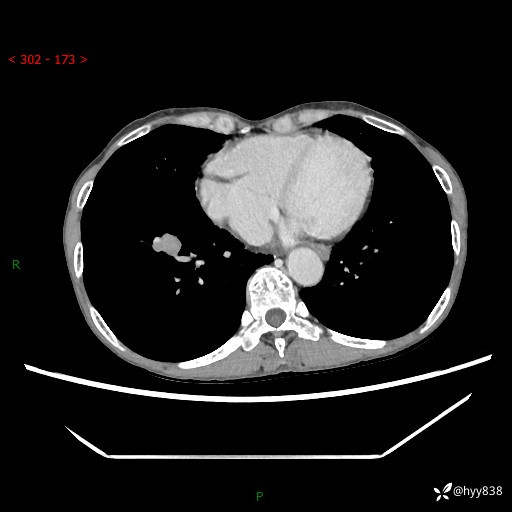

69岁/女,发现肺占位3天余。精彩好病例,请慧诊---(有结果)

【患者信息】:69岁/女

【主诉】:发现肺占位3天余

【现病史及既往史】:患者3天余前因既往肺气肿复查胸部CT发现“右肺下叶结节、双肺多发结节、双肺门及纵膈淋巴结增大”,平素偶有咳白色粘液痰,下肢乏力,无明显低热、盗汗、咯血、胸痛、喘气等不适,今为求明显结节性质遂来我院门诊就诊,门诊以“孤立性肺结节”收治入院。 起病以来,患者精神饮食睡眠一般,大小便正常,体力无明细变化,体重近年来较前下降。

【检查】:胸部CT增强